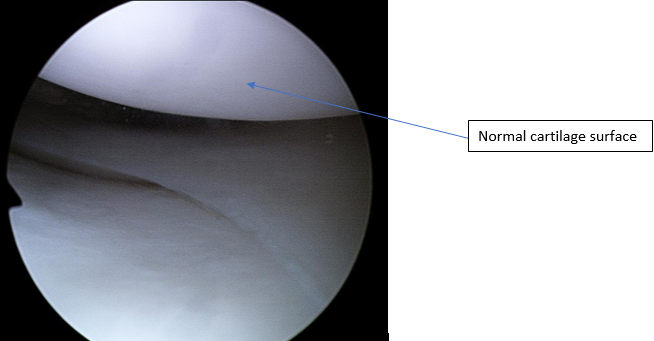

Most joints are lined by a layer of cartilage. In the knee and the hip this cartilage is yaline articular cartilage which is a very smooth and strong type of cartilage. The cartilage is lubricated by a thin layer of fluid (synovial fluid) and this produces a joint surface that has minimal friction and is able to bear a very heavy load for many years.